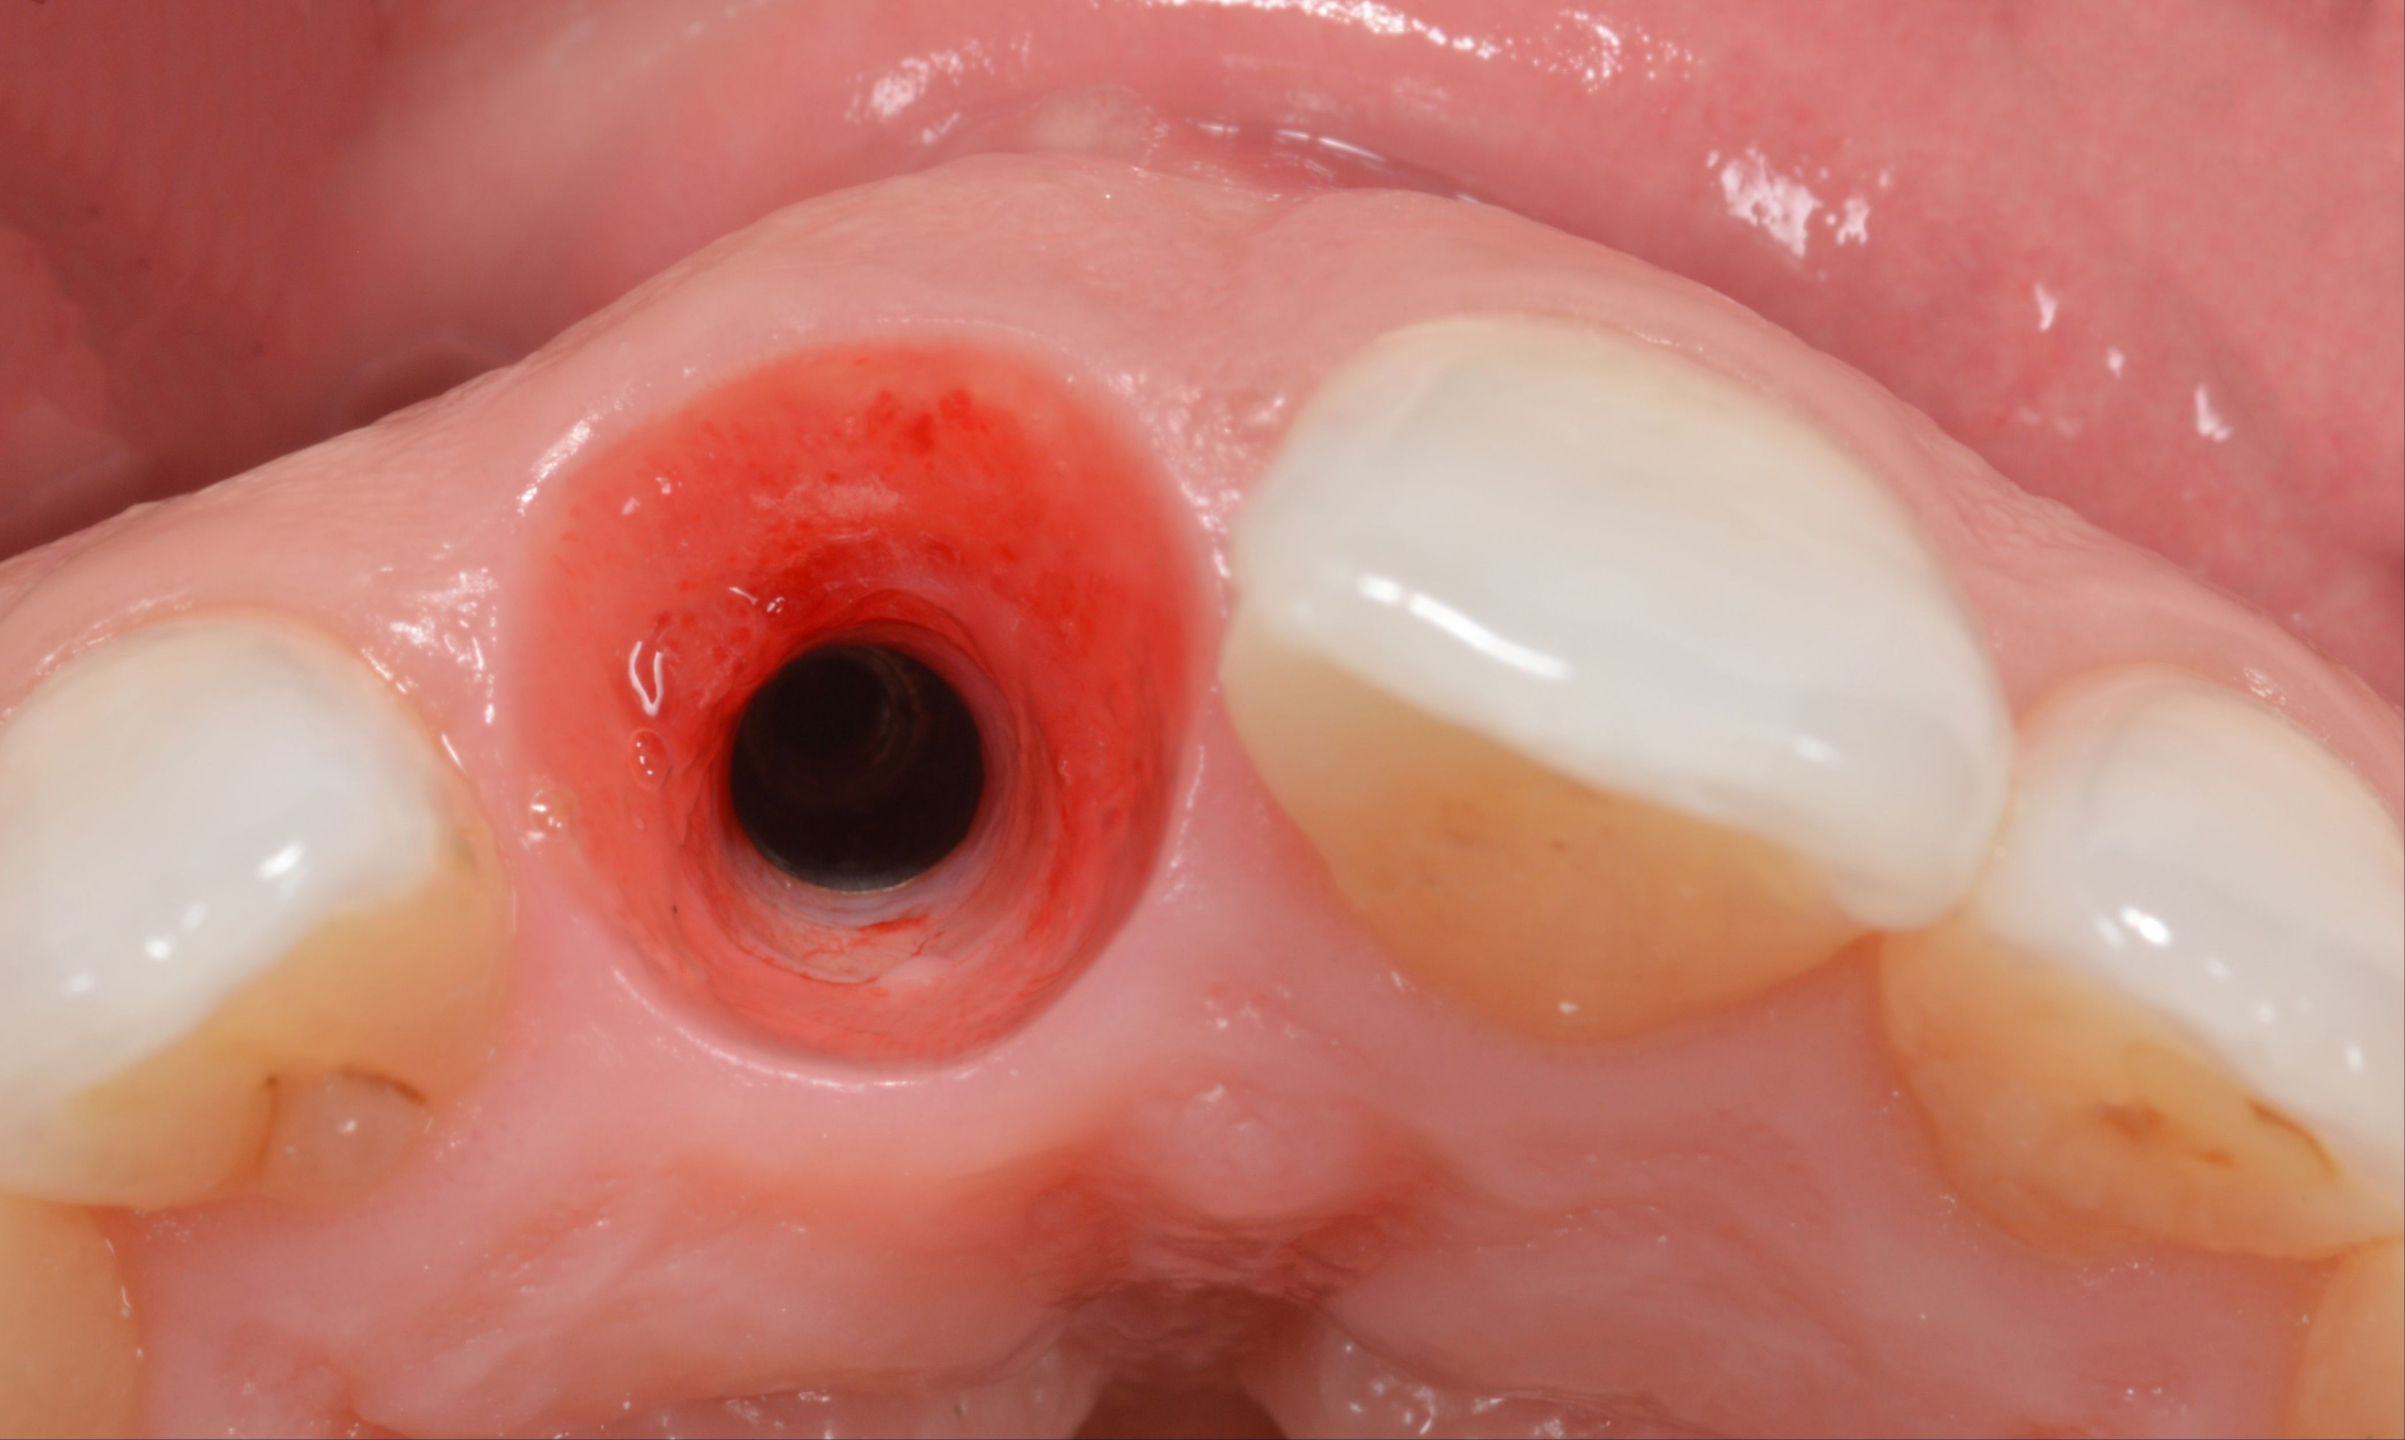

• Sulcular Bleeding at First Disconnection of an Implant Healing Abutment

• Fabrication and use of custom healing abutments